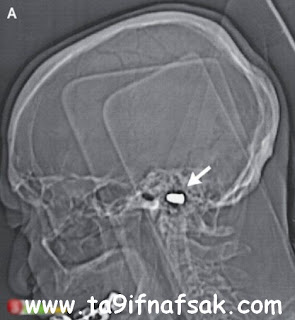

العثور على قدم داخل دماغ طفل!

العثور على قدم داخل دماغ طفل!

أصيب طبيب أميركي بالذهول عندما كان يجري فحصا ميكروسكوبيا لرضيع عمره 3 أيام واكتشف قدما داخل دماغه.

وذكرت مجلة كي ال ايه نيوز، ان الدكتور بول غراب الذي يعمل في مستشفى «ميموريال» للأطفال في منطقة كولورادو سبرنينغز، اكتشف القدم في دماغ الرضيع سام إيسكويبيل خلال عملية لاستئصال ورم فيه، مشيرا إلى أنه وجد أيضا جزءا من الأمعاء قام باستئصاله. وأضاف ان العملية الجراحية التي أجريت للطفل في الثالث من أكتوبر الماضي تكللت بالنجاح.

إلى ذلك، وصف أطباء حالة الطفل بالنادرة، وبأنها أغرب حالة في تاريخ الطب البشري. وكانت أجريت للأم فحوصات التصوير ما فوق السمعي عندما كانت في الأسبوع الـ 41 من الحمل، وعندما تبين أن جنينها يعاني من خلل في الدماغ تقرر إجراء عملية فورية لتوليدها.

يشار إلى أن الطفل يعيش الآن مع والديه وهو بخير حسبما يقول الأطباء